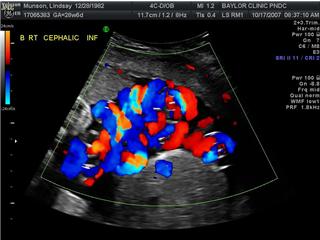

MOMO Cords

These are my babies cords

….a mangled mess